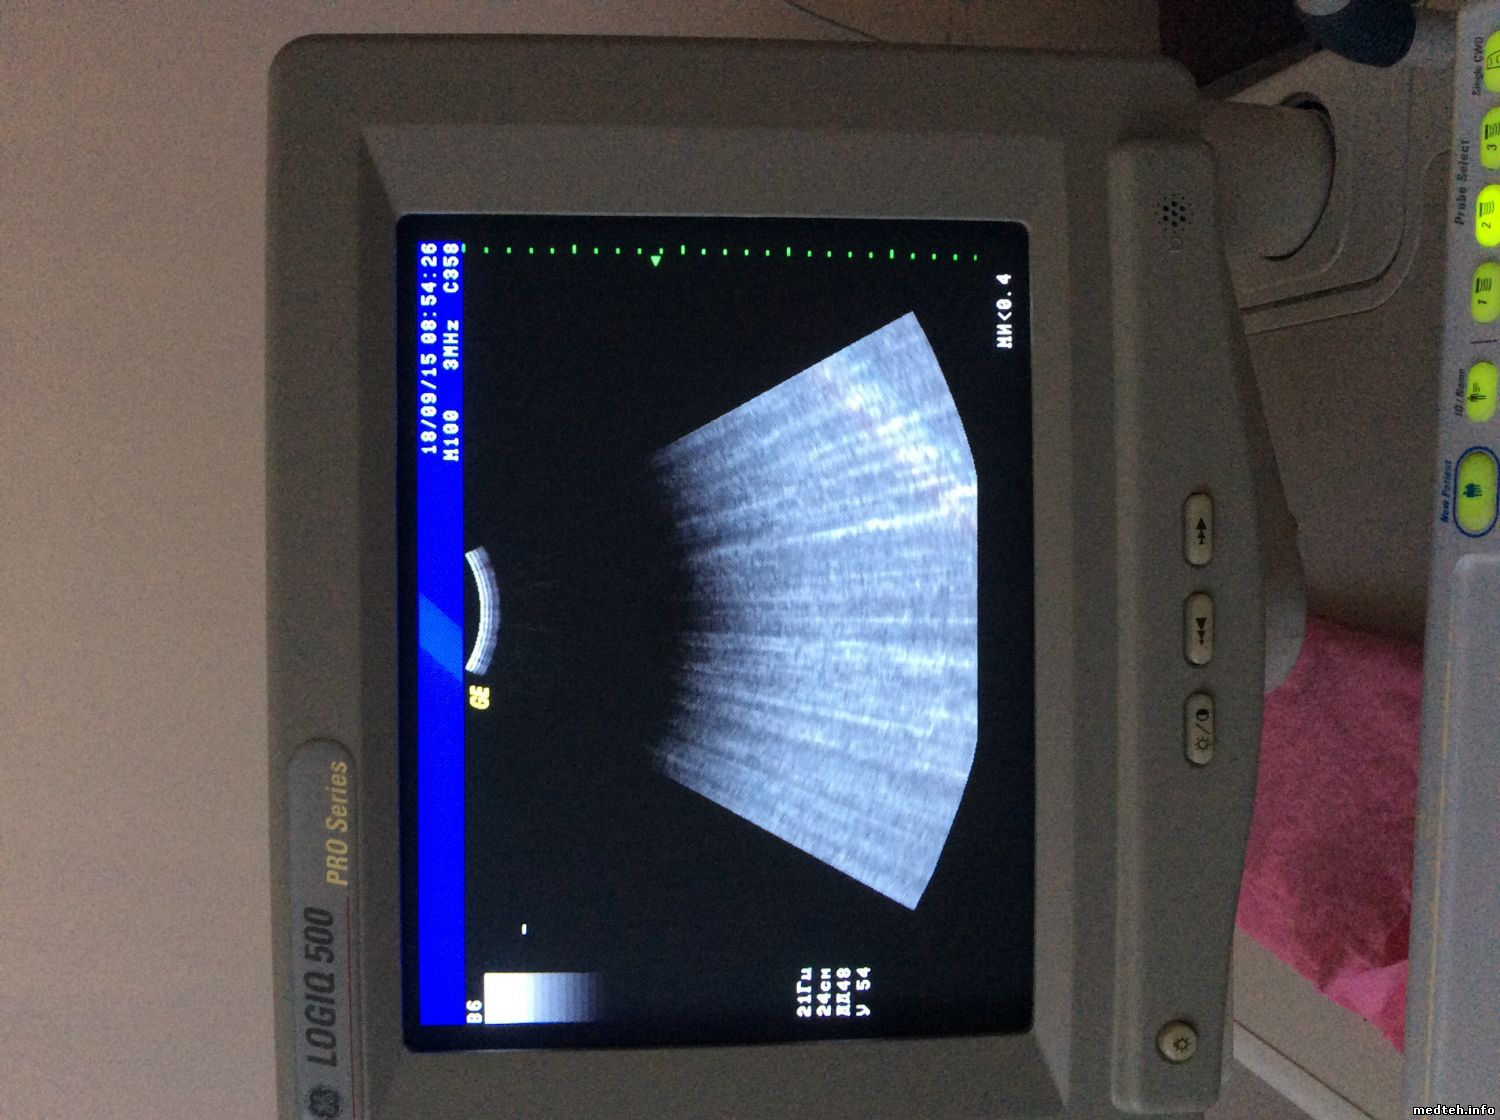

Здраствуйте!Я доктор,работаю на аппарате Logiq 500pro 2006 года выпуска.За время работы на аппарате отмечаются значительные помехи,которые периодически сами пропадают.Работаю в кабинете возле которого есть лифт,хирургическая операционная и еще один узи кабинет.Для устранения этих помех был установленный ИБП Power walker VI 2200,установили сетевой фильтр,заземление от розетки.Но ничего не помагает.Пробывали перетаскивать на другую сторону помещения,но без эффекта. Вот вылаживаю фото:

Подскажите ,пожалуйста,в чем причина этих помех?

4219416.jpg (151.7 Kb) · 2585506.jpg (160.1 Kb) · 7010616.jpg (166.3 Kb) · 0486875.jpg (125.6 Kb)

А у вас помехи только на конвексе или и на других датчиках такое присутствует?

на всех датчиках присутствует